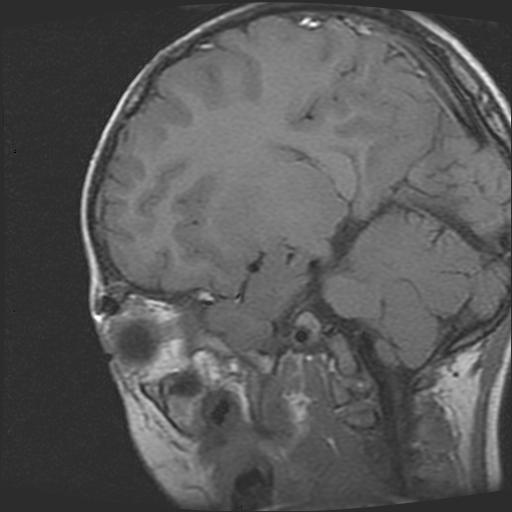

标题: PED0377: 6岁小儿,左侧视神经瘤术后 [打印本页]

标题: PED0377: 6岁小儿,左侧视神经瘤术后

6岁小儿,左侧视神经瘤术后。现左侧视力减退。